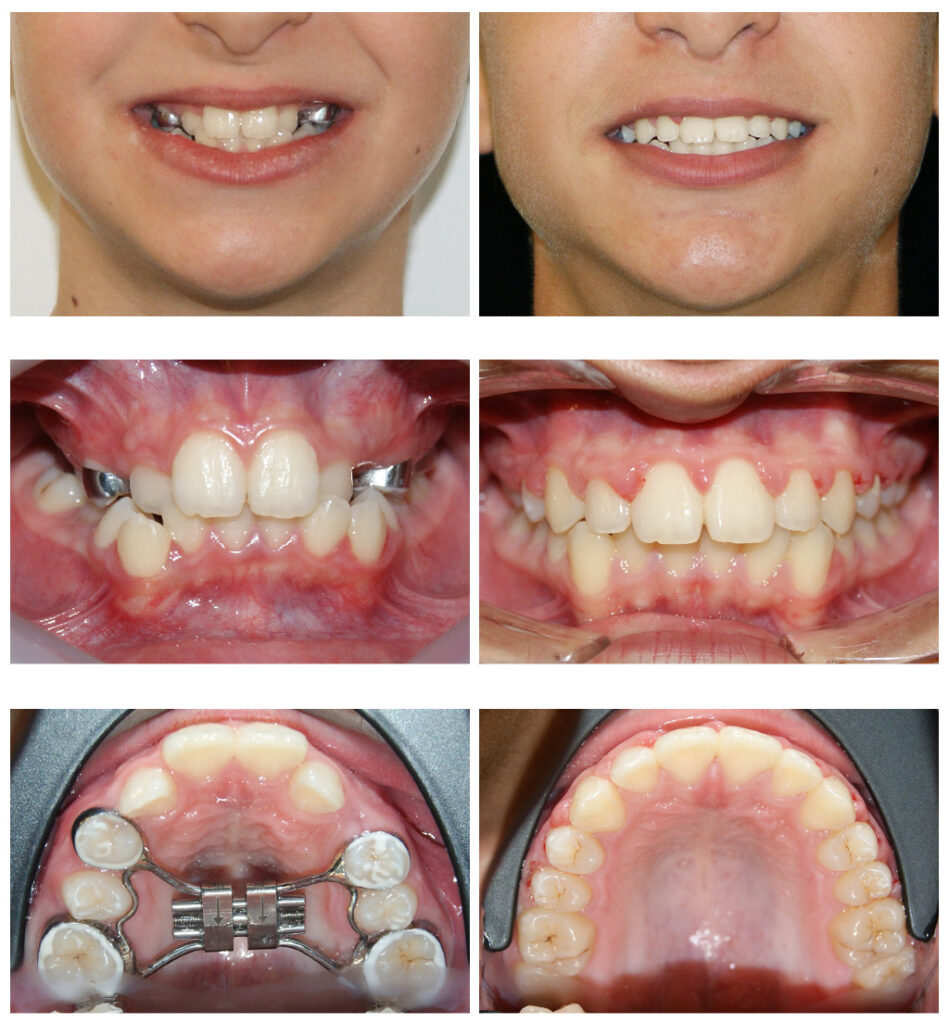

Corectarea muscaturii inverse cu forte extraorale – masca Delaire și disjunctor maxilar Alegem aparatul potrivit la vârsta potrivită

Corectarea muscaturii inverse cu forte extraorale – masca Delaire și disjunctor maxilar. Câteva luni pentru rezultate de care copilul se bucură întreaga viată